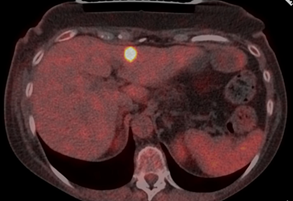

follow-up PET-CT detected in June 2023 the appearance of multiple liver

metastases, involving the segments IVa, III/IVb, V and VI (Figure 1).

Figure 1: PET-CT imaging

at the start of therapy with TDxd, showing one of the liver metastases